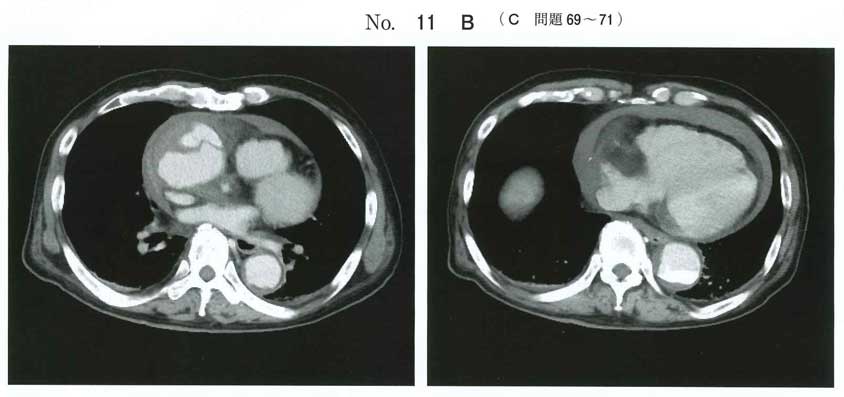

解離 タンポナーデ

心タンポは拡張不全が主体なので、bですね。

心タンポナーデで右心系への流入が妨げられるため、下大静脈は拡張して呼吸性変動が減少する。

右室/右房は拡張期/収縮期に拡張が妨げられ、虚脱(collapse)する。

上行大動脈は拡張している。